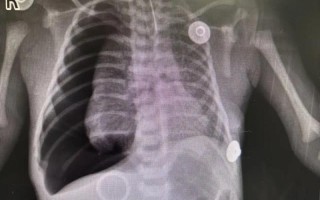

新生儿乳糜胸胸腔积液,病因、诊断与治疗全解析

什么是新生儿乳糜胸?新生儿乳糜胸是指新生儿胸腔内异常积聚了富含乳糜微粒的乳糜液,胸腔:我们的胸腔内有肺和心脏,胸壁内层覆盖着一层薄薄的膜,叫做胸膜,正常情况下,胸膜腔内只有少量润滑液体,让肺在呼吸时能...